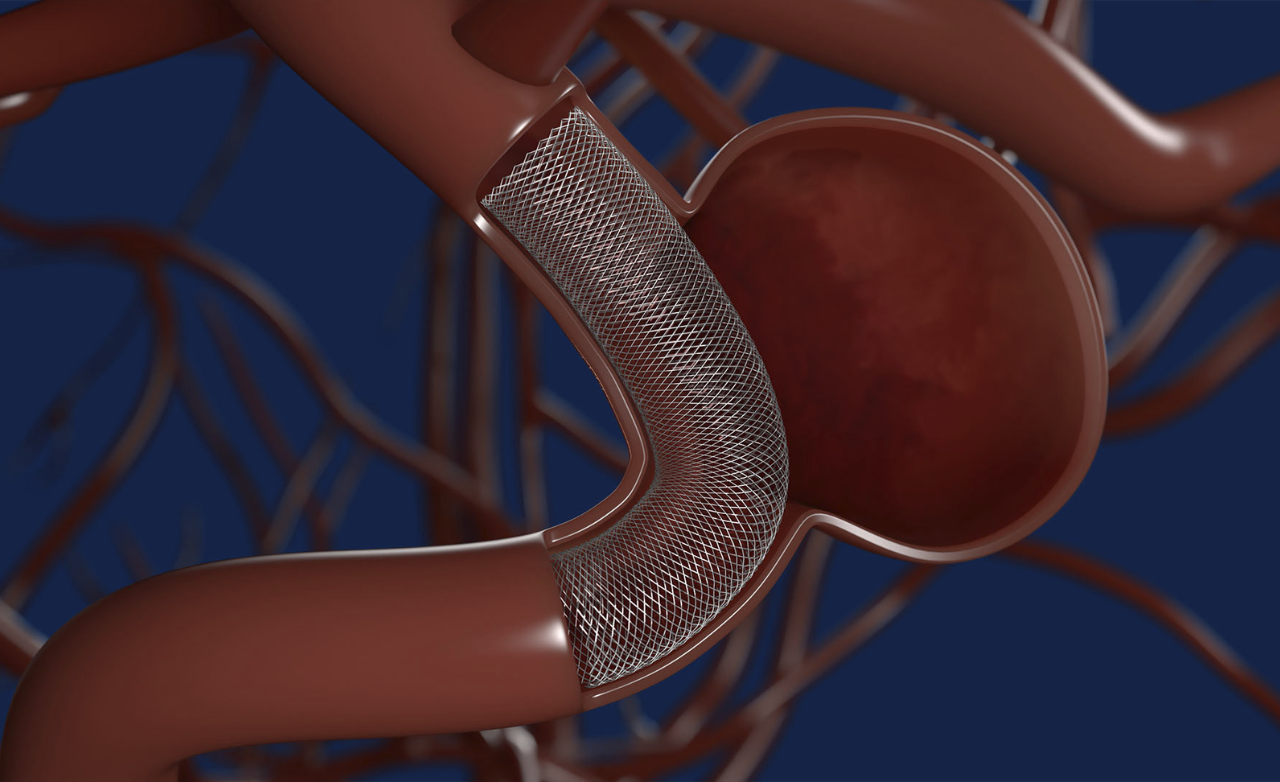

Flow diverter treatment is a minimally invasive procedure used to treat complex brain aneurysms that are difficult to manage with surgery or coiling. It is commonly recommended for wide-neck or hard-to-reach aneurysms.

A special device is placed inside the parent artery to redirect blood flow away from the aneurysm, allowing it to heal naturally while maintaining normal brain circulation.

Enhances treatment by redirecting blood flow away from the aneurysm, promoting gradual healing, improving vessel stability, and ensuring stronger, durable protection against future rupture.